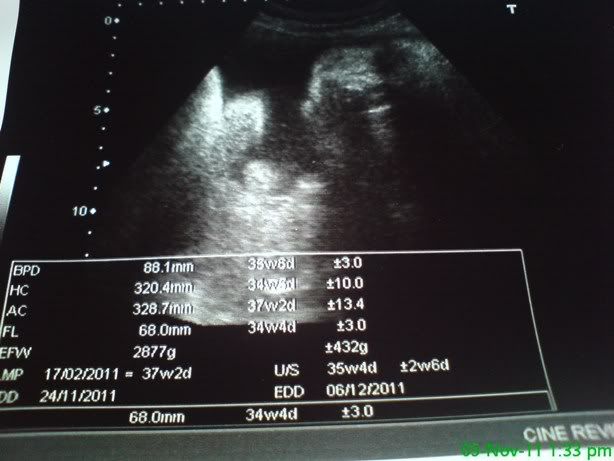

这个星期37周了。。。基本上宝宝已经发育完整,可以出来的。。。现在就等宝宝的心情几时咯。。。看她要选择 ...